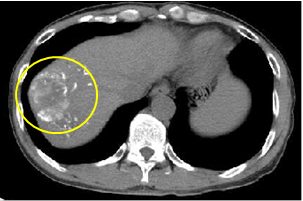

随访图像

术后1个月CT平扫影像可以在肿瘤部位看到白色光亮微球沉积影,表明显影栓塞微球具有良好的持续显影能力,可作为标记物引导后续的治疗如消融治疗、粒子植入、穿刺活检等。